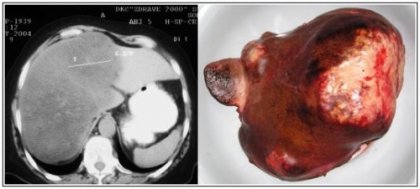

Болести на черния дроб